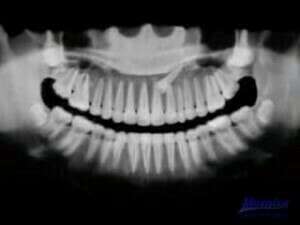

Radiographie - traction orthodontique d'une canine incluse :